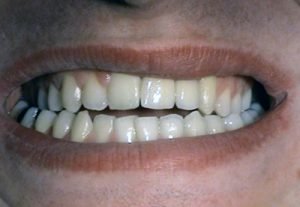

Replacements of individual teeth

Implantation & prosthetics – „all in one“

1. PHASE - implant placement

2. PHASE - before taking prints

3. PHASE - temporal crown before final implant